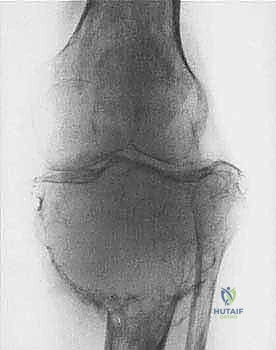

* الساركوما العظمية (Osteosarcoma): الأكثر شيوعاً، تظهر عادة حول الركبة (أسفل الفخذ أو أعلى القصبة).

| حدود الورم في الأشعة | واضحة، محددة بدقة (Sclerotic margin) | غير واضحة، متآكلة (Moth-eaten appearance) |

| اختراق قشرة العظم | نادر جداً | شائع جداً، يمتد للأنسجة الرخوة المحيطة |

جراحة الحفاظ على الأطراف (Limb-Salvage Surgery): الفن والعلم

تعتبر جراحة الحفاظ على الأطراف معجزة طبية حديثة. بدلاً من بتر الطرف المصاب، يقوم الأستاذ الدكتور محمد هطيف بإزالة الورم بالكامل ثم إعادة بناء العظم والمفصل والأنسجة الرخوة. تتكون هذه العملية المعقدة من ثلاث مراحل أساسية:

المرحلة الأولى: استئصال الورم (Resection)

يتم فتح الجلد والأنسجة بعناية فائقة. التحدي الأكبر هنا هو فصل الورم عن الأوعية الدموية والأعصاب الرئيسية المغذية للطرف. يستخدم الدكتور هطيف تقنيات الجراحة الميكروسكوبية لضمان سلامة هذه الهياكل الحيوية، مما يحافظ على حيوية الطرف وحركته.

المرحلة الثانية: إعادة البناء العظمي (Skeletal Reconstruction)

بعد إزالة جزء من العظم (أو المفصل بأكمله)، يجب سد الفجوة. تتعدد الخيارات التقنية التي يوفرها الدكتور هطيف في صنعاء:

1. المفاصل الصناعية الكبيرة (Megaprostheses): مفاصل معدنية متطورة (من التيتانيوم) تُصمم خصيصاً لتعويض العظم المفقود، وتسمح للمريض بالحركة المبكرة.

الحالة الأولى: إنقاذ ساق شاب رياضي

شاب في العشرينيات عانى من ساركوما عظمية في أسفل عظمة الفخذ. كان التشخيص المبدئي في مراكز أخرى هو البتر. بفضل التقييم الدقيق، أجرى الدكتور هطيف جراحة استئصال واسع للورم مع تركيب مفصل ركبة صناعي مخصص للأورام (Tumor